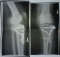

ich war weniger als 5 Monate nach der OP 10 Tage Skifahren ohne Pausentag bei besten Schneeverhältnissen (rot, blaue und schwarze Pisten). Also noch mit Metall drin. Nächste Jahr aber gerne mit Pausentag: Sauna und Wellness muss auch sein :-)

Es ist nichts dick geworden, nichts tut weh - ganz im Gegenteil, das Knie fühlt sich sogar geschmeidiger an. Ich muss aber sagen, dass ich schon kurz nach der OP mit leichten Übungen angefangen habe (isometrisch, um den Bruch nicht zu belasten) und so schnell es ging die Belastung gesteigert hatte und nach 2 Monaten ohne Krücken unterwegs war und mich eigentlich - bis auf zum Bus/Bahn rennen - dann nicht mehr zurückgehalten habe (s. meinen Thread viewtopic.php?f=2&t=639). Rennen geht immer noch nicht soo gut, wird aber immer besser.

Ich lese derzeit nur ab und zu hier im forum mit :? . Irgendwie schade, aber für mich gibt es einfach nicht viel Neues zum Mitreden. Möchte aber deine Fragen beantworten. Also für mich geht gottseidank jede Art von Sport wieder, die OP ist allerdings schon über 7 Jahre (Metallentfernung über 6 Jahre) her. Ich bin auch im 1. Jahr (mit Erlaubnis vom Arzt) mit den 7 Schrauben im Knie wieder Skifahren und Rennrodeln gewesen, und habe auch einige Rennen (ein bischen gebremst) bestritten. Obwohl ich mich super vorbereitet habe, war das Skifahren zwar möglich, aber nicht so wie ich es eigentlich gewohnt war (kraftvolles carven) sondern eher ein fröhliches "herunterwedeln". Aber es ging, auch mehrere Tage z.b. 5 hintereinander, ohne Schmerzen. Die Kraft fehlte allerdings und das Knie war einfach nicht so ganz stabil wie früher, auch wenn ich im Alltag gar nichts mehr spürte. Vermutlich habe ich einfach unbewusst das Knie geschont und hatte ein wenig Angst - Kopfsache. Erst nach dem 2. Jahr ging es merklich besser, ab dem 3. Jahr ohne Einschränkungen :mrgreen: .

Joggen habe ich im 1. Jahr komplett unterlassen (dafür viel Rad gefahren), aber so ab dem 2. und 3. Jahr hatte ich keine Probleme mehr mit dem Joggen, auch lange Bergtouren mit Abwärtslaufen (nicht nur Abwärtsgehen) waren wieder möglich. Heuer bin ich 14 Rodelrennen gefahren, Bilder auf sportrodeln.at